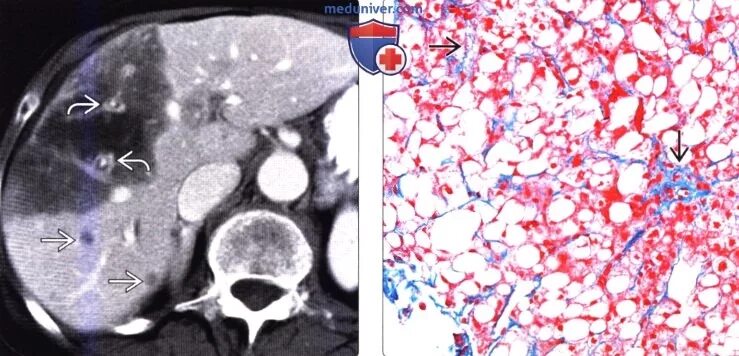

Диффузные изменения паренхимы по типу стеатоза